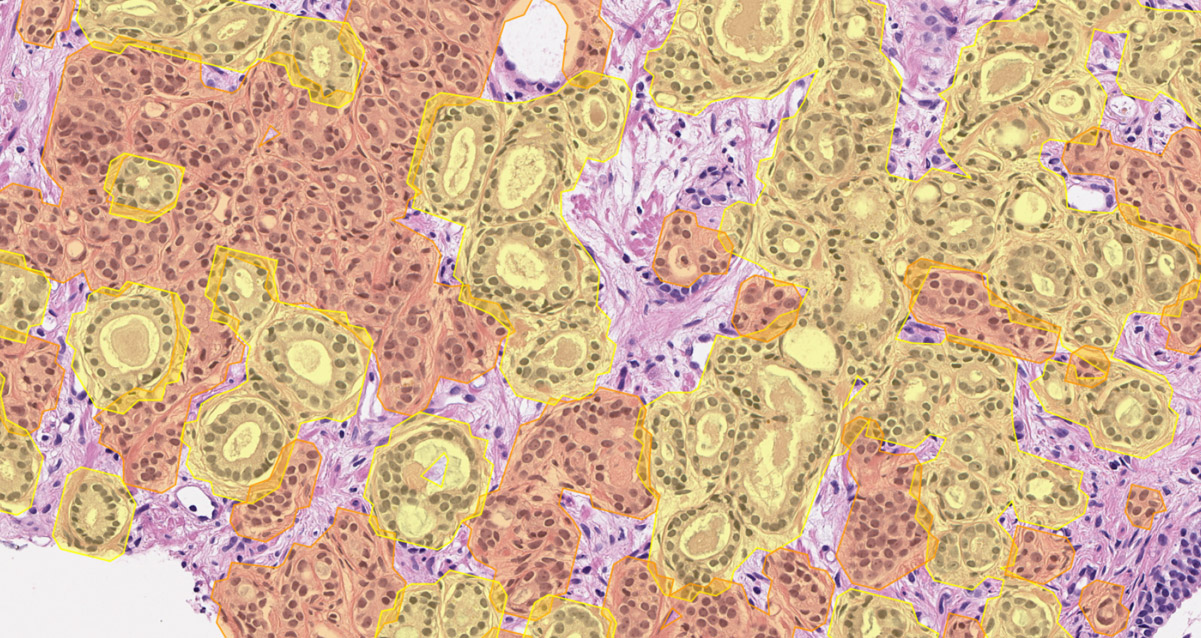

DeepDx® Prostate can be used in a variety of use settings including first read, concurrent read, quality control, research and development, and education.

Pre-filled pathology reports are generated once slides are analyzed using DeepDx® Prostate. Clinically significant information included in the pathology report includes:

•   Gleason scores

•   Relative proportions of each Gleason pattern

•   Percentage involvement of cancer in tissue

Quantitative metrics such as tumor-to-tissue ratios and Gleason pattern ratios are recalculated in real-time as annotations are made.

Sample images representative of the cancer found in a slide.